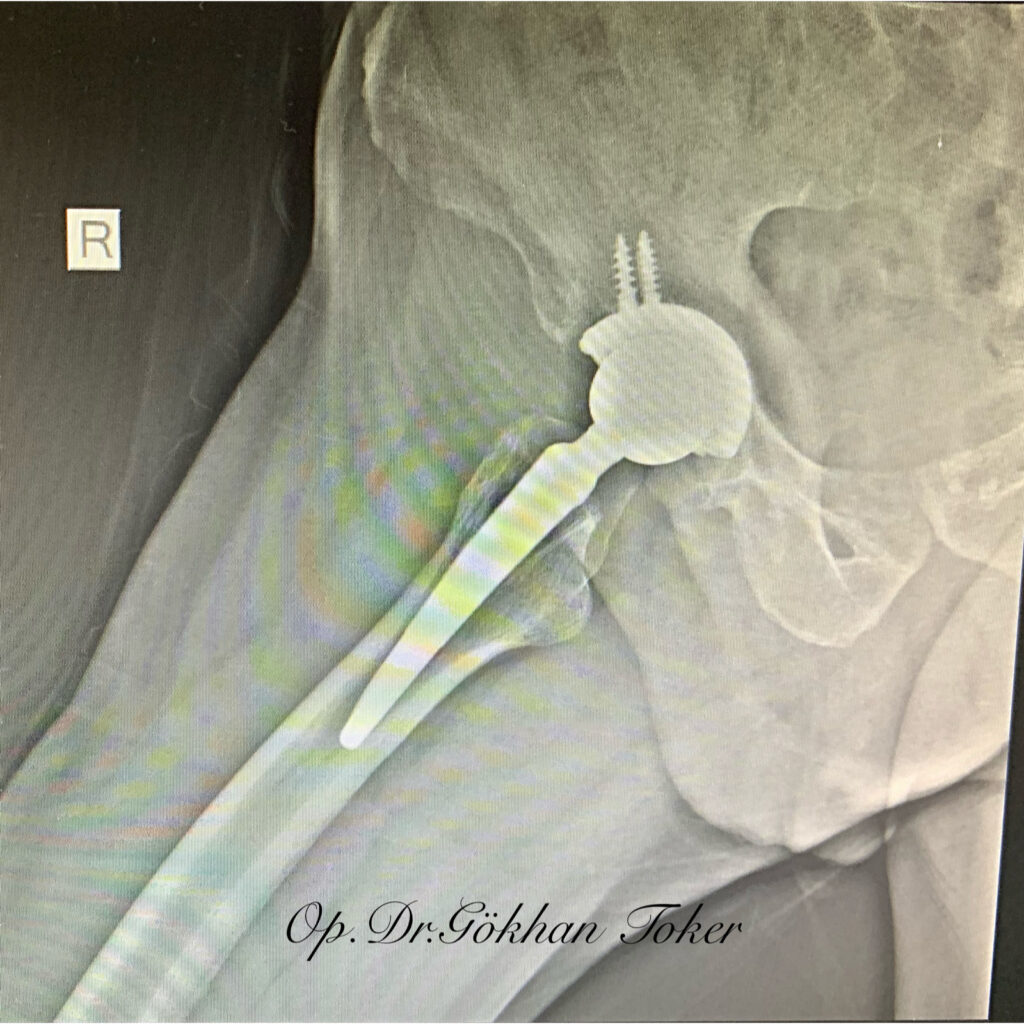

Ç.A.